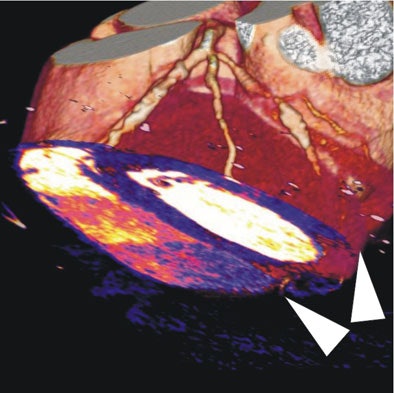

| In a 64-year-old man with chest pain, image of the corresponding slice shows inferior ischemia (arrows). |